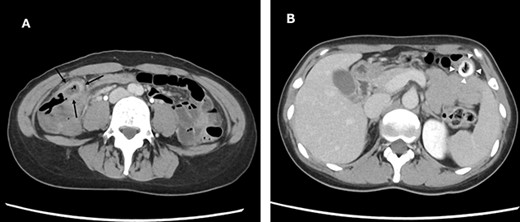

A 38-year-old woman presented with lower right abdominal pain of 3 days duration before the consultation. She had a history of left ovarian cystectomy and no history of medication use or allergies. She was 172-cm tall and weighed 59.0 kg. On examination, there was right lower abdominal pain with no rebound tenderness. The white blood cell count was 13 600 /μl, and the C-reactive protein was 3.8 mg/dl. Contrast-enhanced computed tomography (CT) revealed a 4-cm cecal diverticulum with inflammation and a fecalith (Fig. 1). An abscess penetrated through the mesenteric side and was localized in the mesentery. The diagnosis was cecal colonic diverticulitis and classified as Hinchey II. The abdominal symptoms were localized; hence, the patient was treated with antibiotics. From Day 1 of hospitalization, she was on nil per oral and administered CMZ at 3 g/day. On hospitalization Day 3, the right lower abdominal pain improved, and contrast-enhanced CT imaging was performed. The cecal colonic diverticulitis improved, and the fecaliths migrated to the transverse colon (Fig. 2). Moreover, the inflammatory reaction improved. In a multidisciplinary meeting, we discussed that the patient should undergo a detailed examination, including colonoscopy, and elective surgery after readmission. However, we suggested that surgical treatment should be performed as early as possible after considering the risk of early recurrence and bleeding. The patient wished to undergo minimally invasive surgery; thus, we performed an immediate ileocolectomy and lymphadenectomy using SILS as we did not rule out the likelihood of malignant disease.

Abdominal and pelvic CT on hospitalization Day 3. Axial images (A and B) showing improved cecal colon diverticulitis (black arrows); however, fecaliths migrated to the transverse colon (white arrowheads).